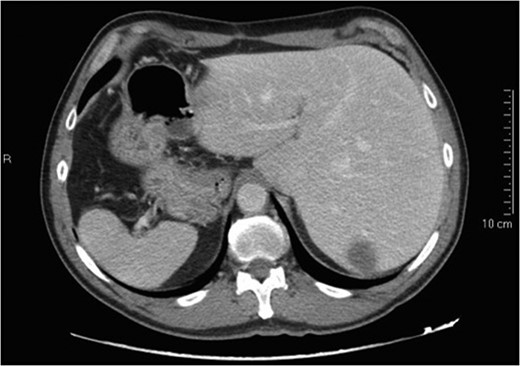

Situs inversus totalis (SIT) is a congenital condition consisting of a mirror image of transposition of the abdominal and thoracic organs occurring in about 1:5000 to 1:10 000 adults. We report on a 60-year-old male with a single colorectal liver metastasis in the Segment 7. The patients underwent a totally laparoscopic sub-segmentectomy. Intraoperative approach on a reverse posterior segment was difficult because of left-sided position of the liver. Postoperative course was uneventful and the patient was discharged after 5 days. To our knowledge, only a few cases of open liver resections in patients with SIT have been published. This is, therefore, the first case of laparoscopic liver resection for colorectal liver metastasis in a patient with SIT. We provide the readers with useful tips to perform minimally invasive liver surgery in such patients.

Situs inversus is a congenital condition with an incidence ranging between 1:1000 and 1:10 000 characterized by left-to-right transposition of one or more normally asymmetrical organs of the body. Situs inversus totalis (SIT) consists of a mirror-image transposition of the abdominal and thoracic viscera, which occurs in about 1:5000 to 1:10 000 adults [1]. Patients affected by SIT are usually completely asymptomatic, but they have more commonly major defects which can shorten their lifespan [1].

These observations are even more true for a patient with previous open surgery and an SIT with the double challenge related to the anatomic position of the liver and the posterior (7) segment involved. Another challenging maneuver was the separation of the liver from the diaphragm; the absence of any ligament made this part of the procedure very demanding to identify the correct plane from the diaphragm and the liver and minimize the bleeding.